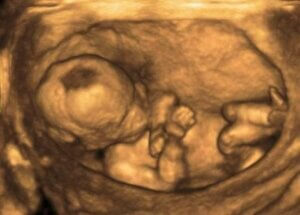

의료 전문가는 일반적으로 초음파 검사를 통해 양수의 양을 측정함으로써 그 변화를 파악한다. 양수지수 (AFI)를 통해 진단하는 것이다.

필요한 정보를 수집하기 위해 전문가는 자궁을 4등분으로 구분해서 센치미터 단위로 측정한다. 정상 양수지수는 8~21 cm 이다.